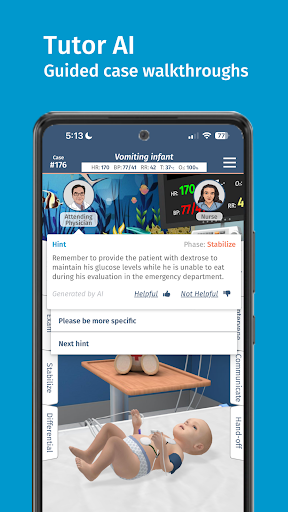

-- Tutor AI --

Gợi ý Mã đầy đủ giờ đây thậm chí còn hữu ích hơn! Được hỗ trợ bởi AI tổng hợp, nhân vật bác sĩ điều trị hiện đóng vai trò là người hướng dẫn, cung cấp thông tin tổng quan chi tiết và gợi ý cụ thể trong từng trường hợp để giúp bạn vừa học vừa chơi.

-- Hướng dẫn từng trường hợp --

Với mức độ khó Dễ được cập nhật của chúng tôi, Tutor AI có thể cung cấp hướng dẫn tương tác cho từng trường hợp, hướng dẫn bạn kiểm tra, điều trị và chẩn đoán cùng với các giải thích chi tiết về từng bước quan trọng.